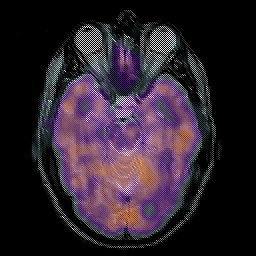

Glioma overlay -- Slice #10

[Home][Help][Clinical] Slice 10